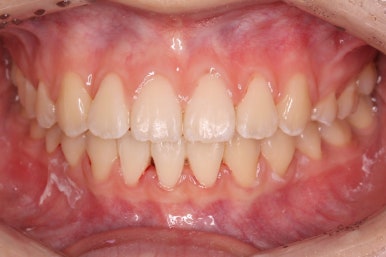

부산교정 키다리아저씨치과에서 결손치아 부분을 임플란트 하지 않고 치아교정을 통해서 개선한 이번 환자분의 치료를 마무리한 사진입니다.

치열은 가지런해졌고, 틈새는 없이 마무리되었습니다. 아랫니가 3개이지만 마치 4개인 것처럼 마무리하였고, 따라서 위~아래 치열의 중앙도 거의 맞게 마무리하였습니다.

(한 쪽은 송곳니를 앞니 대신 사용해야 했어서 크기 문제로 완벽히는 중앙을 맞추기 힘듭니다.)